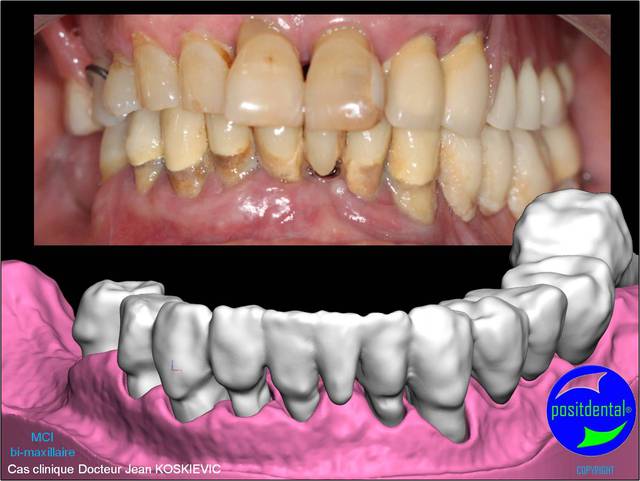

photo pré opératoire

rendu 3D maxillaire sup, pano et photo

3D maxillaire inférieur et photo